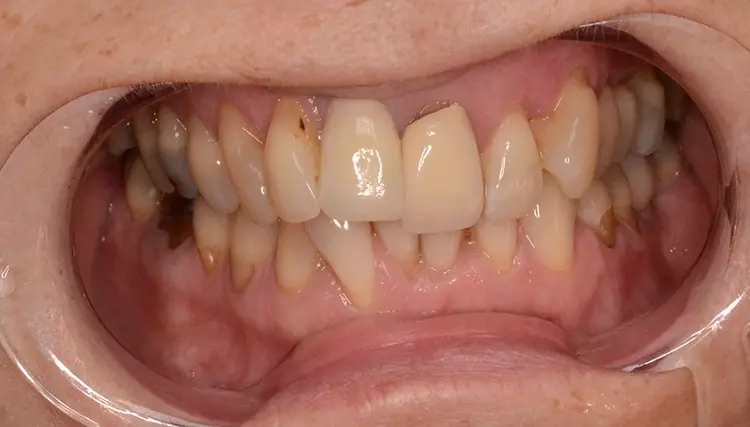

Bei dem heute 49-jährigen Patienten wurde seit Kindertagen versäumt, die Ober- und Unterkieferzahnbögen kieferorthopädisch auszurichten. Der Patient leidet seitdem stark unter seinen Zahnfehlstellungen.

Die Fraktur des stark elongierten Zahnes 21 war für den Patienten der Ausgangspunkt, sowohl die Front des Ober- als auch des Unterkiefers prothetisch überarbeiten zu lassen. Dabei wurde der frakturierte Zahn 21 durch ein navigiert eingesetztes Sofortimplantat ersetzt, während die verschachtelt stehenden Zähne 12 und 42 durch eine Brückenversorgung korrigiert wurden (Abb. 4a-j).